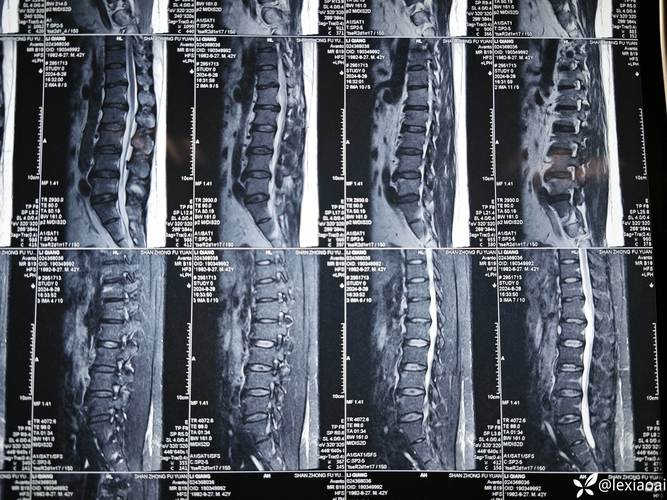

当您或您的医生提到“风湿性脊柱炎要做核磁共振”时,实际上指的是为强直性脊柱炎患者进行MRI检查。

核磁共振能看到什么?(关键影像表现)

在强直性脊柱炎的MRI报告中,医生主要会寻找以下几种特征性的改变:

核磁共振检查的序列

为了全面评估,强直性脊柱炎的MRI检查通常会包含以下序列:

检查部位

根据病情阶段和医生怀疑的部位,MRI检查可能包括:

- 骶髂关节:必查项目,这是诊断AS的起点,通常做冠状位和轴位扫描。

- 脊柱:包括颈椎、胸椎、腰椎,主要用于评估脊柱的活动性炎症、椎体病变以及晚期的强直情况。